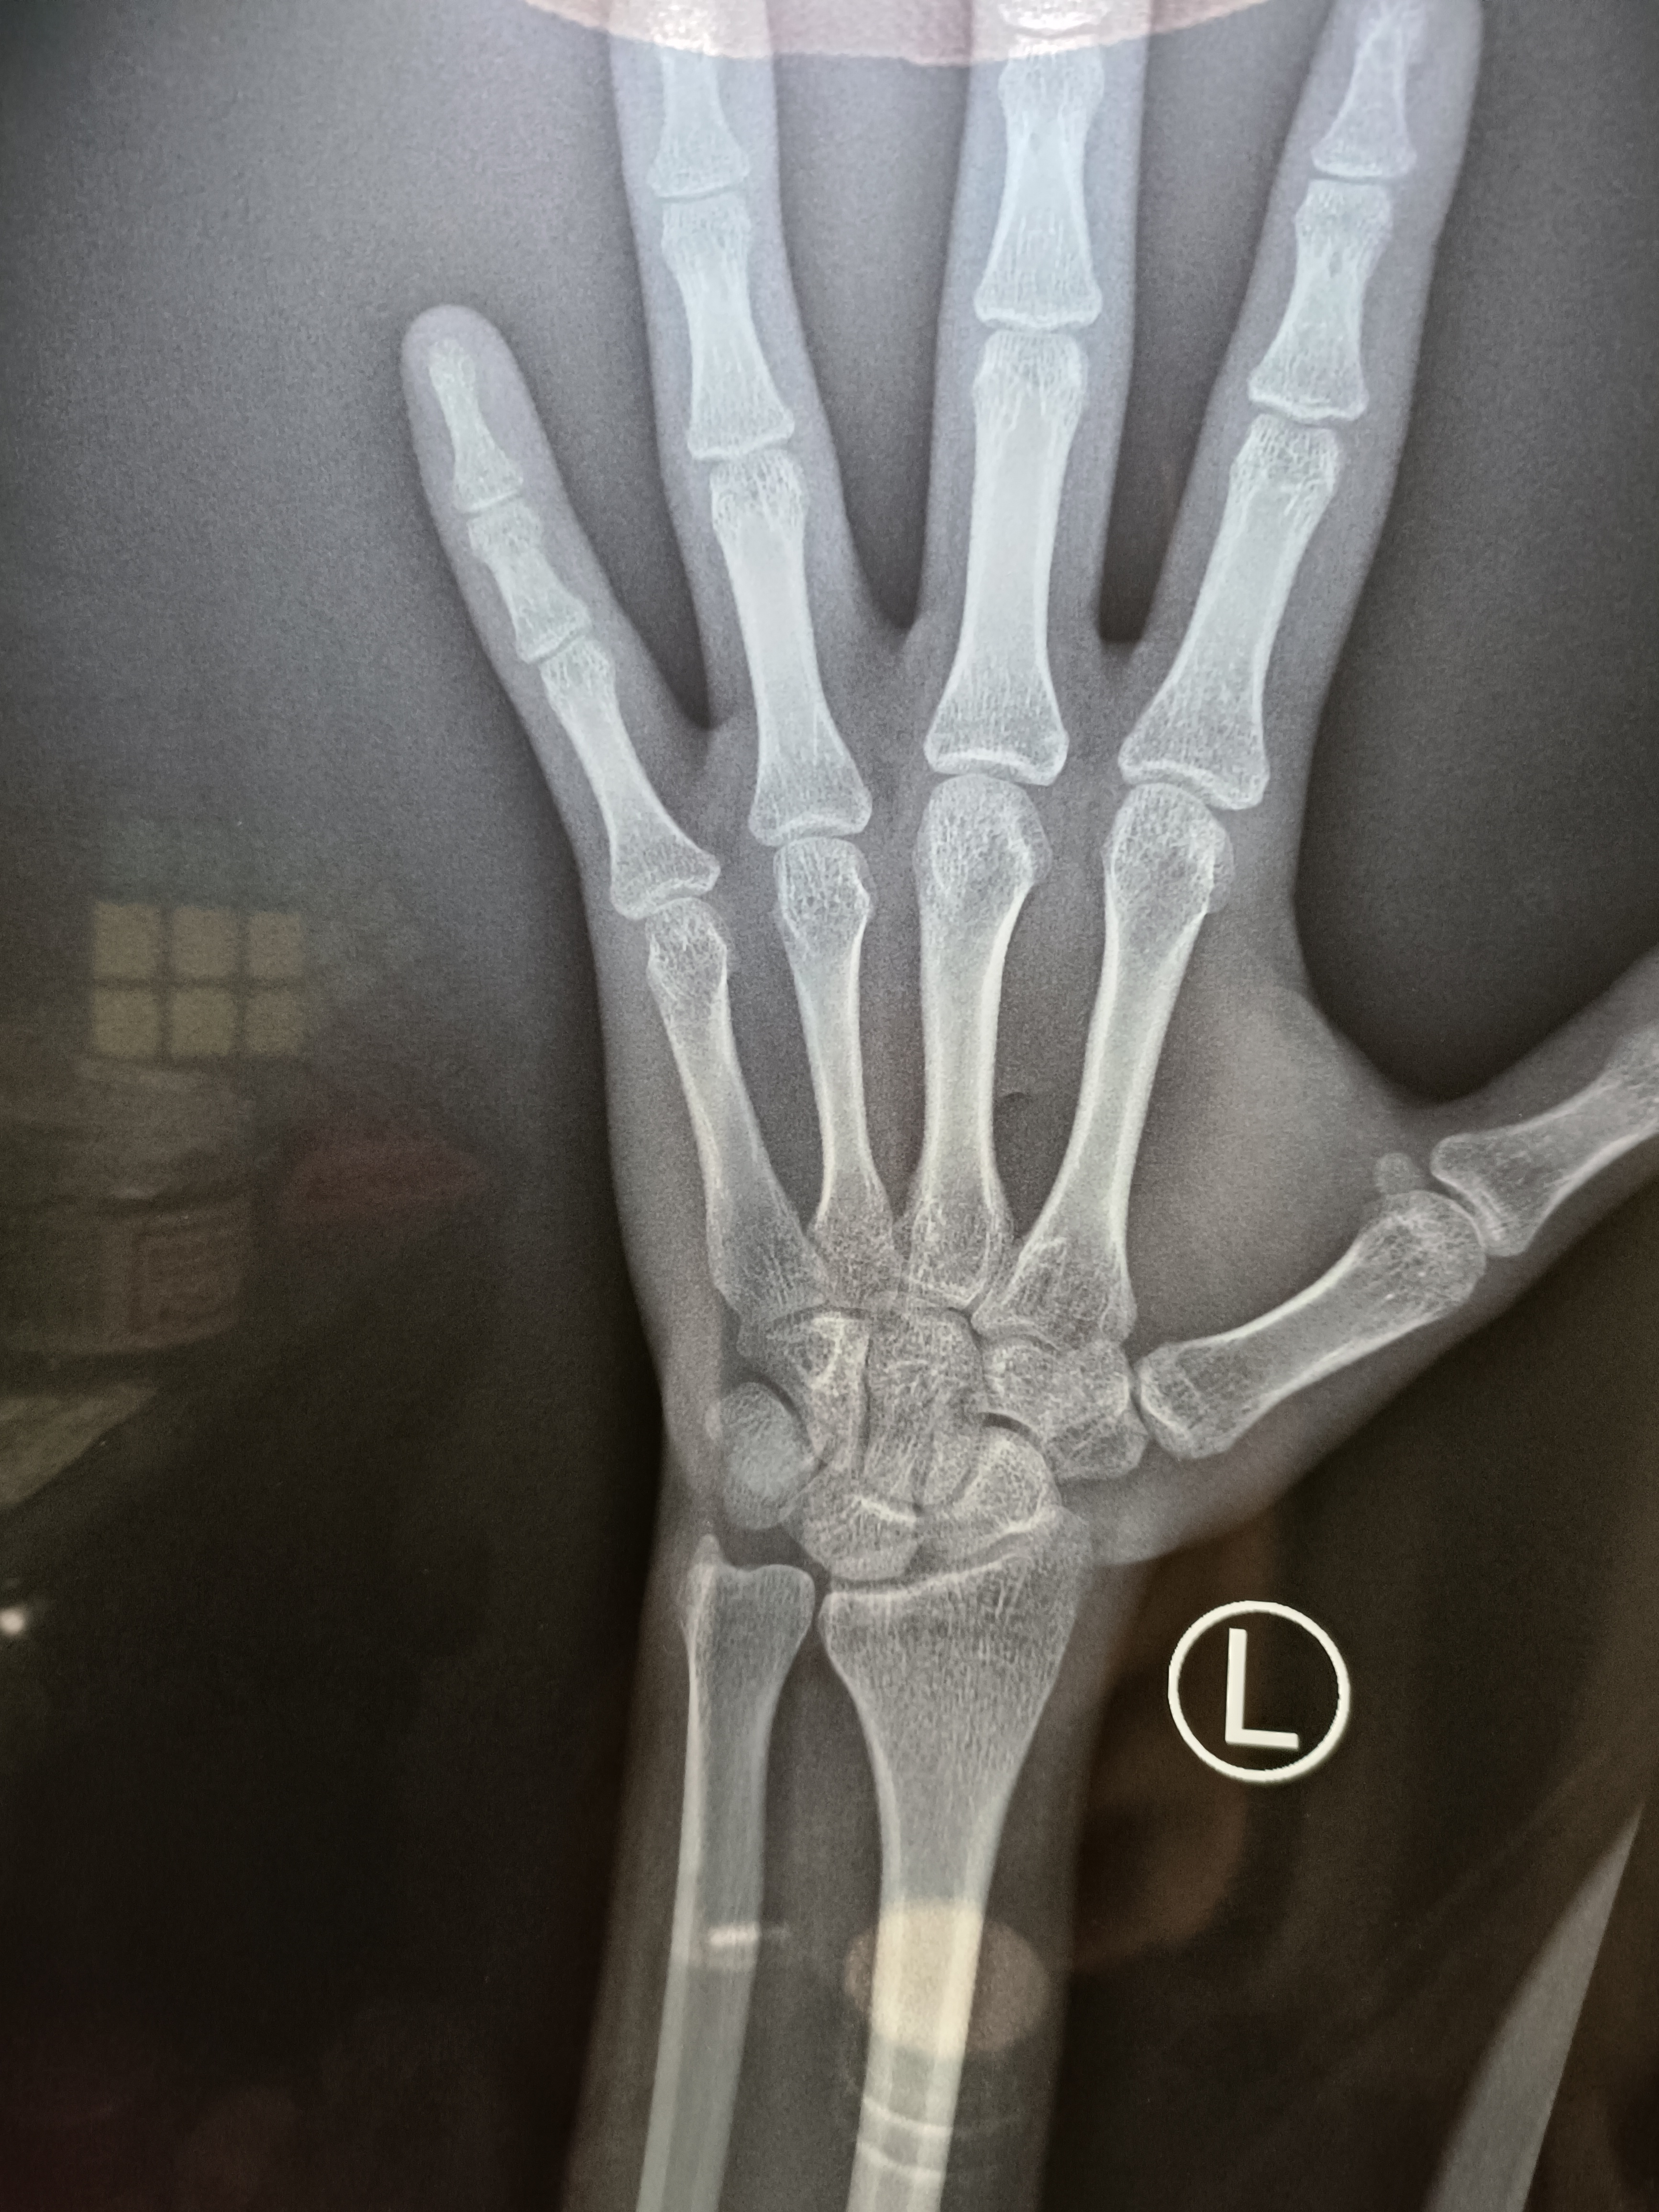

我觉得不对劲,把孩子拉过来看了看,果不其然,孩子已经进入青春期,*丸睾**也开始发育了,他现在这种情况,骨龄肯定是比年龄大的,所以马上建议家长带着孩子去拍个骨龄片,确定一下骨龄大小。

前几天妈妈拿着片子来复诊,我用中华05给孩子评估,果不其然,孩子骨龄已经11.9岁了,比年龄大了将近2岁。按照骨龄来评估,孩子目前身高在10百分位,按照这个生长曲线,孩子成年终身高很可能在165左右,妈妈当时就说不出话了,这对她来说,无疑是一个晴天霹雳。